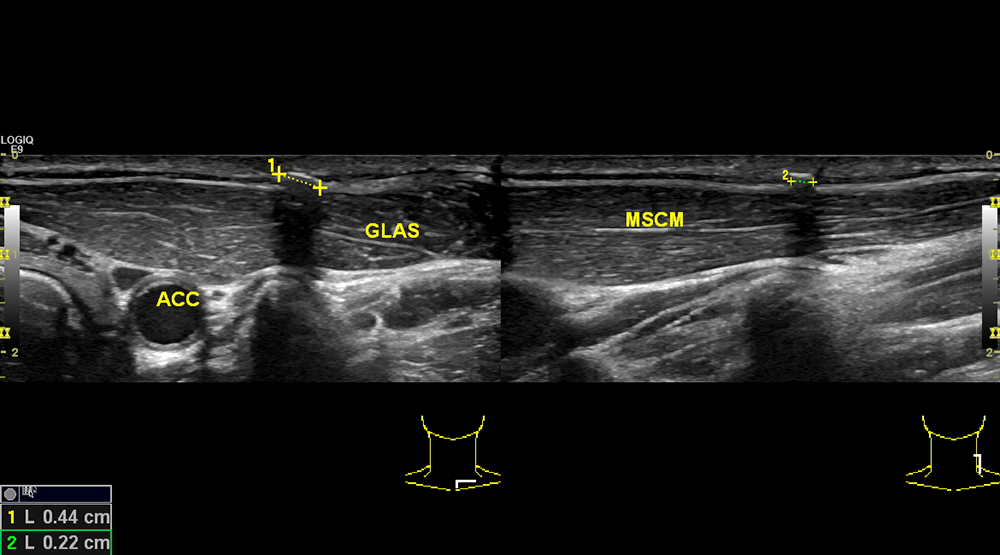

Why Should We Implement CEUS in our Clinical PracticeJuly 15, 2020Student Image Challenge 61July 31, 2020 Student Image Challenge 60 Student Image Challenge #60 1 / 1 Student Image Challenge #60 A 47 yo man with a history of neck trauma has the following ultrasound image. What is your diagnosis? Zenker's diverticulum Paraganglioma Residual foreign body Thyroglossal duct cyst Abscess Incorrect ....Please see the correct answer highlighted Correct: Residual foreign body In B-mode ultrasound appears hyperechoic with posterior shadowing (it can often demonstrate reverberation artifact). Your score isThe average score is 100% LinkedIn Facebook VKontakte 0% Restart quiz Case courtesy of PD Dr. med. Julian Künzel EFSUMBAdmin Related postsStudent Image Challenge 111Read more Comments are closed.